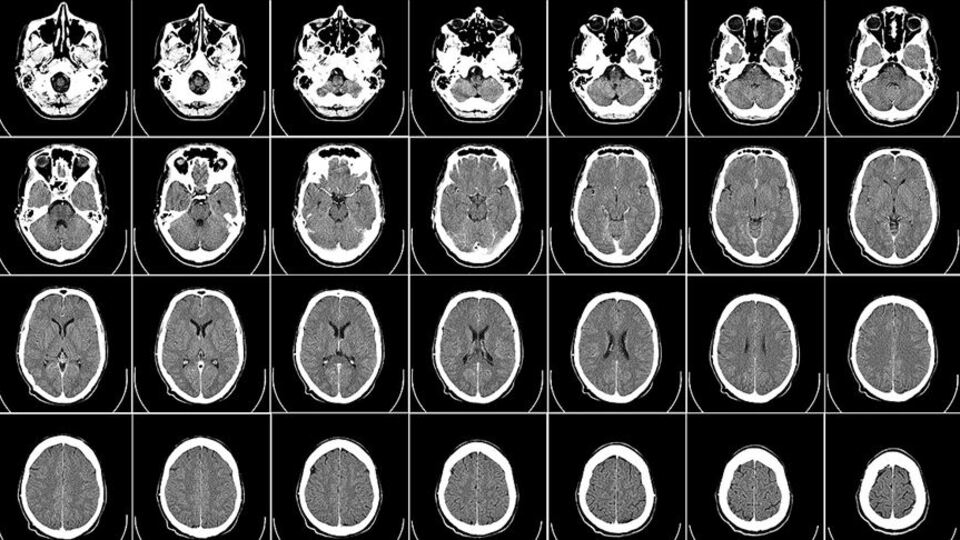

Newatlas sitesinin haberine göre, Cambridge Üniversitesinden bilim insanlarının, yaşları 9 ila 11 olan toplam 2 bin 700 çocuğun verilerini inceleyerek yaptıkları araştırmada, obez çocuklar ile normal kilodaki çocukların beyin yapılarında farklılıklar olduğu tespit edildi.

Çalışma çerçevesinde, obez çocukların beyinlerindeki prefrontal korteks bölgesinde incelme tespit edildiği, bu incelmenin de karar verme, kendini kontrol etme ve duyguların düzenlenmesi gibi davranışları olumsuz yönde etkilediği belirtildi.

Obezitenin beynin çalışma kapasitesine doğrudan etki yaptığını ortaya koyan çalışmada, obezite tedavisi gören ve kilo kaybeden kişilerin bilişsel kapasitelerinde gelişme gözlendiği de hatırlatıldı.

Uzmanlar, obezitenin mi beynin yapısına etki ettiğinin yoksa beyin yapısının mı obeziteyi tetiklediğinin gelecekte yapılacak araştırmalarla tespit edilebileceğinin altını çizdi.